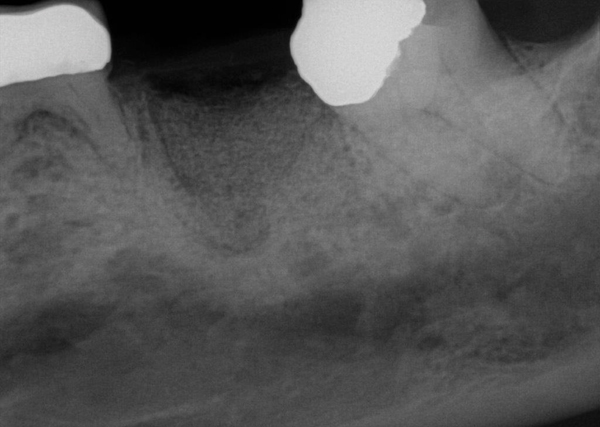

Fig 15. (Case 3) Radiograph of tooth No. 19, which had a hopeless prognosis.

Figure 15

Fig 16. Radiograph of extraction socket. Buccal and lingual plates were defective.

Figure 16